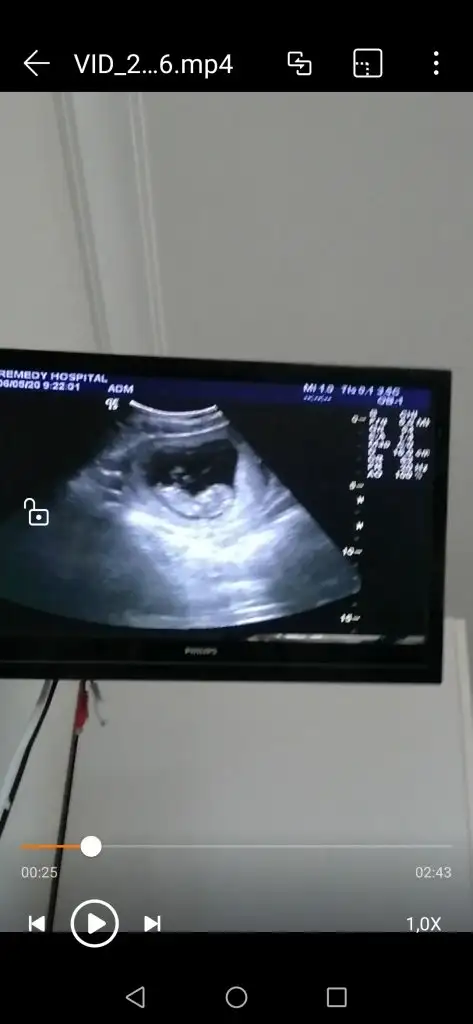

Aynen daha iyi ise usg net tahmin edilirEn net olan buydu ama yarın tekrar kontrolüm var 12+4 olacak olmazsa onu atarım![]()

Net değil sanki erkek gibi siz yinede 12-13 hafta usgde paylaşın11+3 günlük gebeyim rica etsem babada cinsiyet tahmini yapabilir misiniz?

Erkek gibi 12-13 hafta olursa paylaşın11+1 yorumlar mısınız![]()